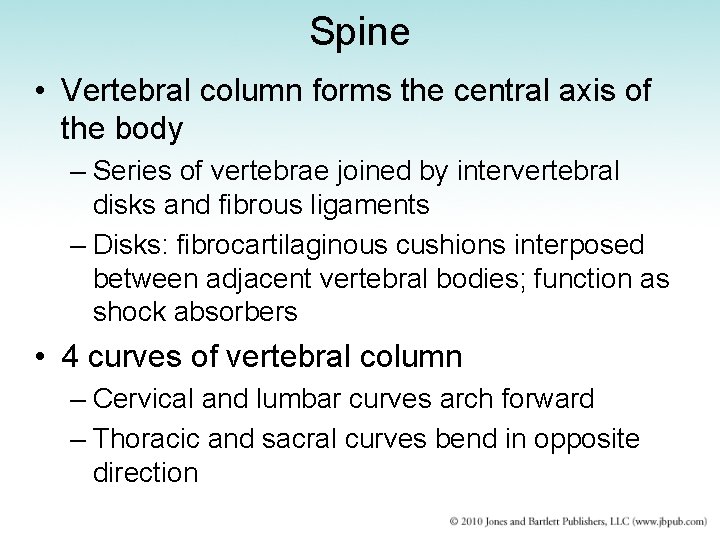

Spine • Vertebral column forms the central axis of the body – Series of vertebrae joined by intervertebral disks and fibrous ligaments – Disks: fibrocartilaginous cushions interposed between adjacent vertebral bodies; function as shock absorbers • 4 curves of vertebral column – Cervical and lumbar curves arch forward – Thoracic and sacral curves bend in opposite direction